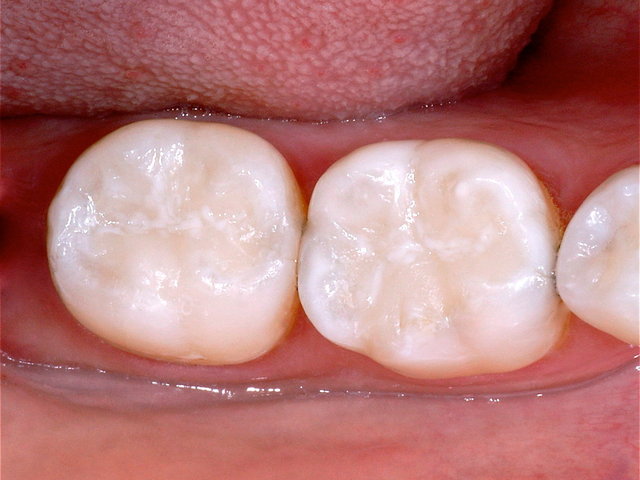

Alte Amalgam-Füllungen mit Sekundärkaries ...

Composit-Füllungen by CLINICDENT ✓